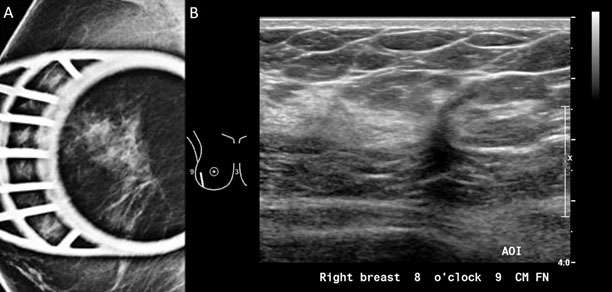

Mammography: Masses Figure 6

Figure 6: A) Spiculated mass was visualized in the right breast with spot compression view on mammogram. B) Sonographic evaluation of the right breast was performed in the region of the mammographic finding. At the 8:00 position 9 cm from the nipple, there is an irregular hypoechoic solid mass with indistinct margins oriented antiparallel to the chest wall demonstrating posterior shadowing, BI-RADS Category: 4C suspicious finding. Pathology confirmed invasive ductal carcinoma, Grade 1.